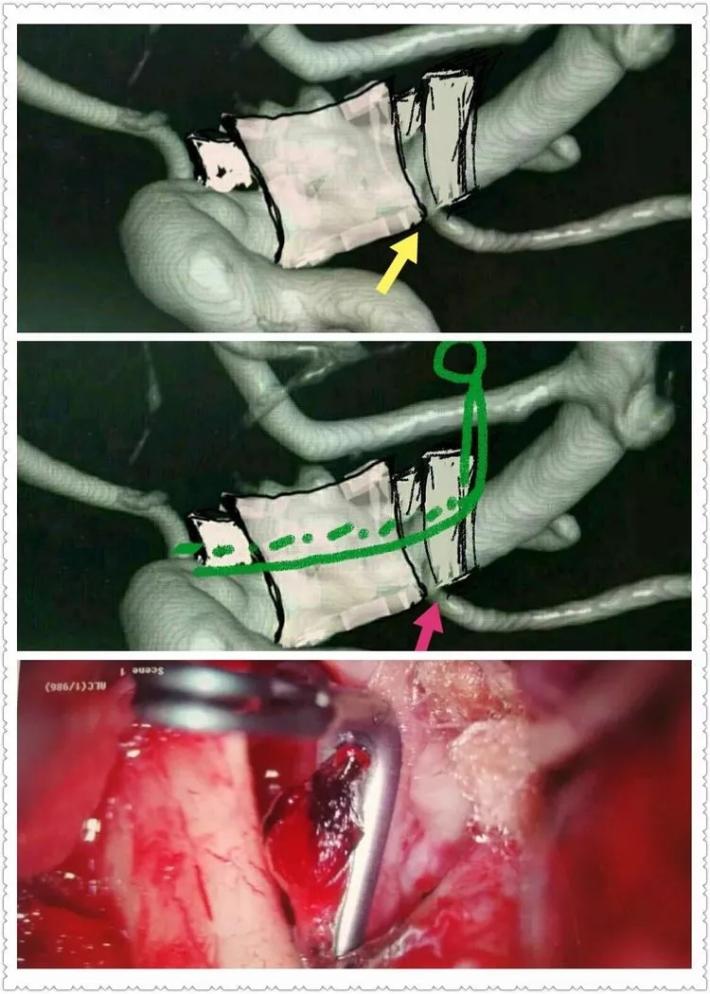

二次复合手术中DsA,黄箭→BBA,白箭→M1,绿箭→STA,M1由于痉挛与STA管径相当,病人有部分开放的前交通,所以本例我们采取的策略是①单支STA一M2搭桥②ICA颅外段阻断③BBA包裏夹闭or孤立④如包裏夹闭失败行孤立术则行STA一M2双支搭桥。

将自体硬膜片包绕BBA段颈内动脉,7号滑线缝合四角为术中包裹夹闭提供牵引以方便操作!

阻断A1后提起7号滑线牵引硬膜补片,自远端放置752动脉瘤夹一枚,探查见近端BBA及硬膜补片夹闭不全!

并行自752夹子上方向近端置742动脉瘤夹一枚,并列自硬膜补片外侧夹闭BBA,手术顺利! 那么脉前A怎么保全呢?

脉前A的保留是术中的一个难题,我们采取硬膜瓣半侧开叉(黄箭头),让脉前A(粉红箭头)由开叉处穿出,避免包裹夹闭后扭曲压迫而致闭塞,术中拟在阻断IcA颅外段与同侧A1的低灌注压状态,采用“L”型异形夹多可顺利夹闭BBA,保留后方脉前A通畅!